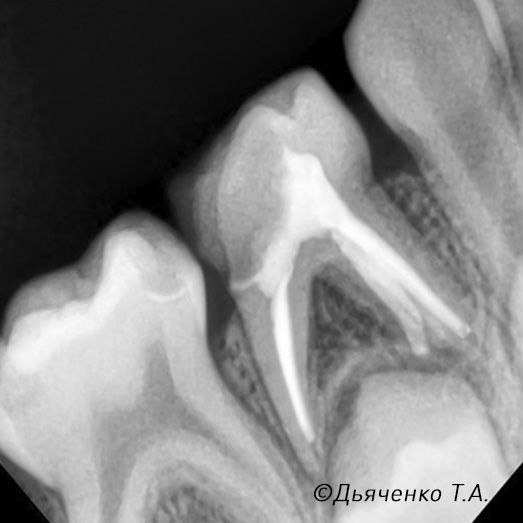

При обширном воспалении нерва, когда воспаление необратимо, может потребоваться его полное удаление с очисткой и пломбированием каналов (рис. 2 и 3).